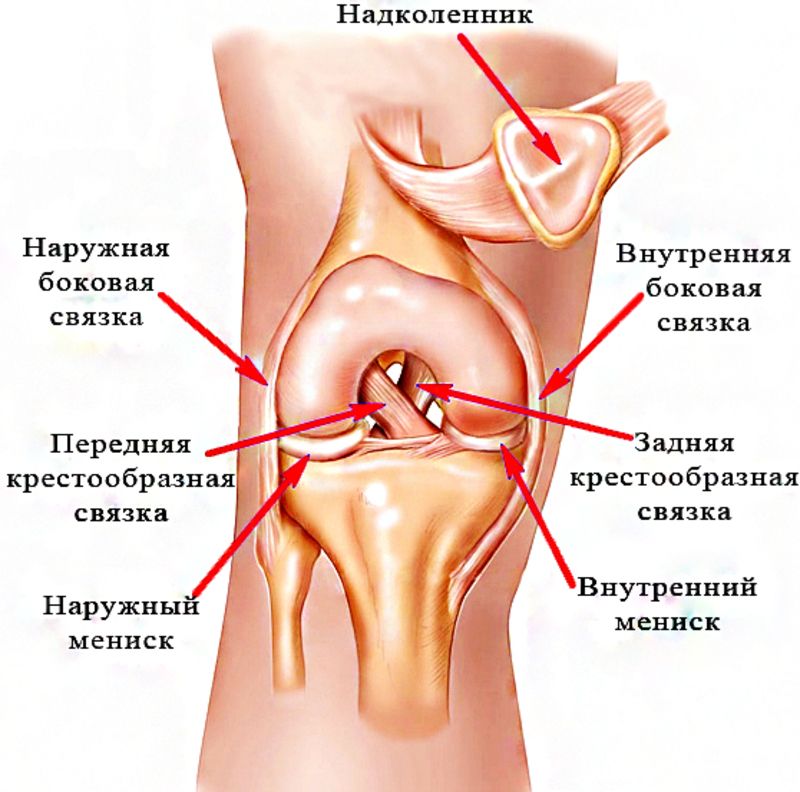

Анатомия коленного сустава: изучение анзерита и его влияния